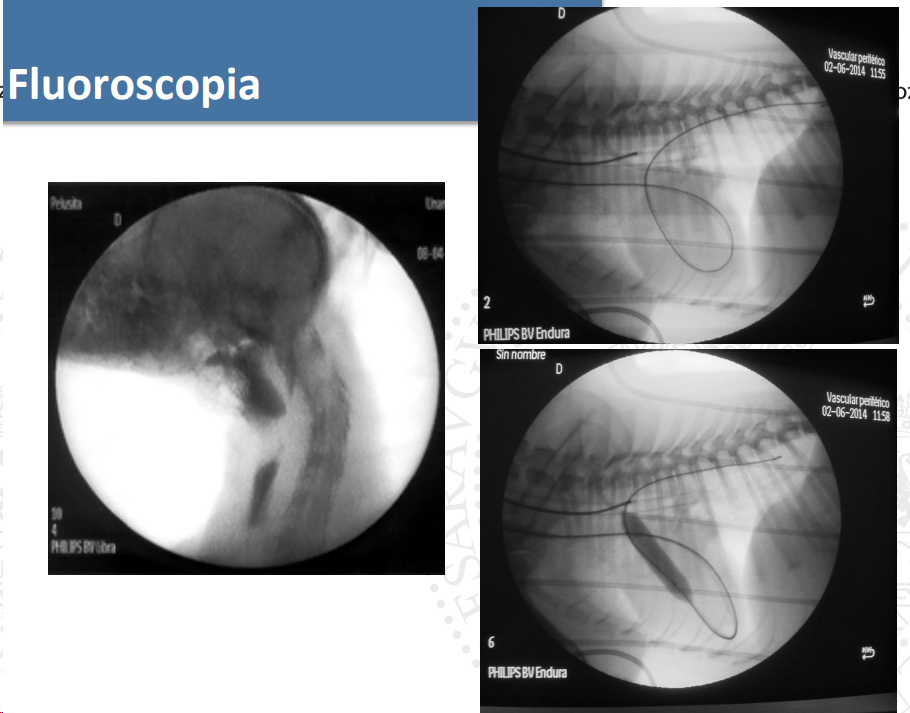

El revelado de la placa puede ser manual o automático con reveladora, para la visualización se usa un negatoscopio. Para intensificar la imagen se usan pantallas fluorescentes; esto reduce la dosis absorbida, pero reduce la resolución y aumenta el ruido. Sirve para estudios en movimiento, imágenes de menor tamaño e invertidas. Se usa sistema de telefisión.

Los arcos de fluoroscopia de componen de: